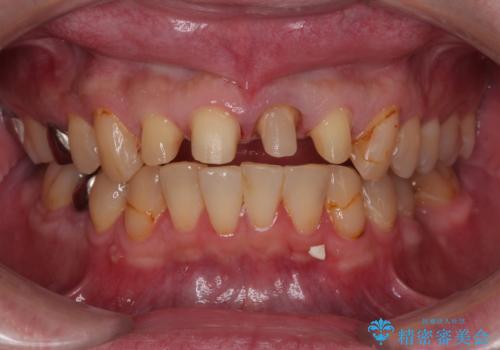

- 前歯の見た目を良くしたいとのことで来院された患者様です。今までに保険のプラスチック(コンポジットレジン)で虫歯の治療をしており経年的な劣化により着色が目立つようになっていました。また歯と歯の隣り合っているところに段差もあり虫歯になっていたり、詰め物も外れていたため前歯4本のオールセラミッククラウンによる治療を行うこととなりました。

拡大鏡視野下で保険のプラスチック(コンポジットレジン)、虫歯、左上1の被せものを除去し、オールセラミッククラウンに適した形にしました。